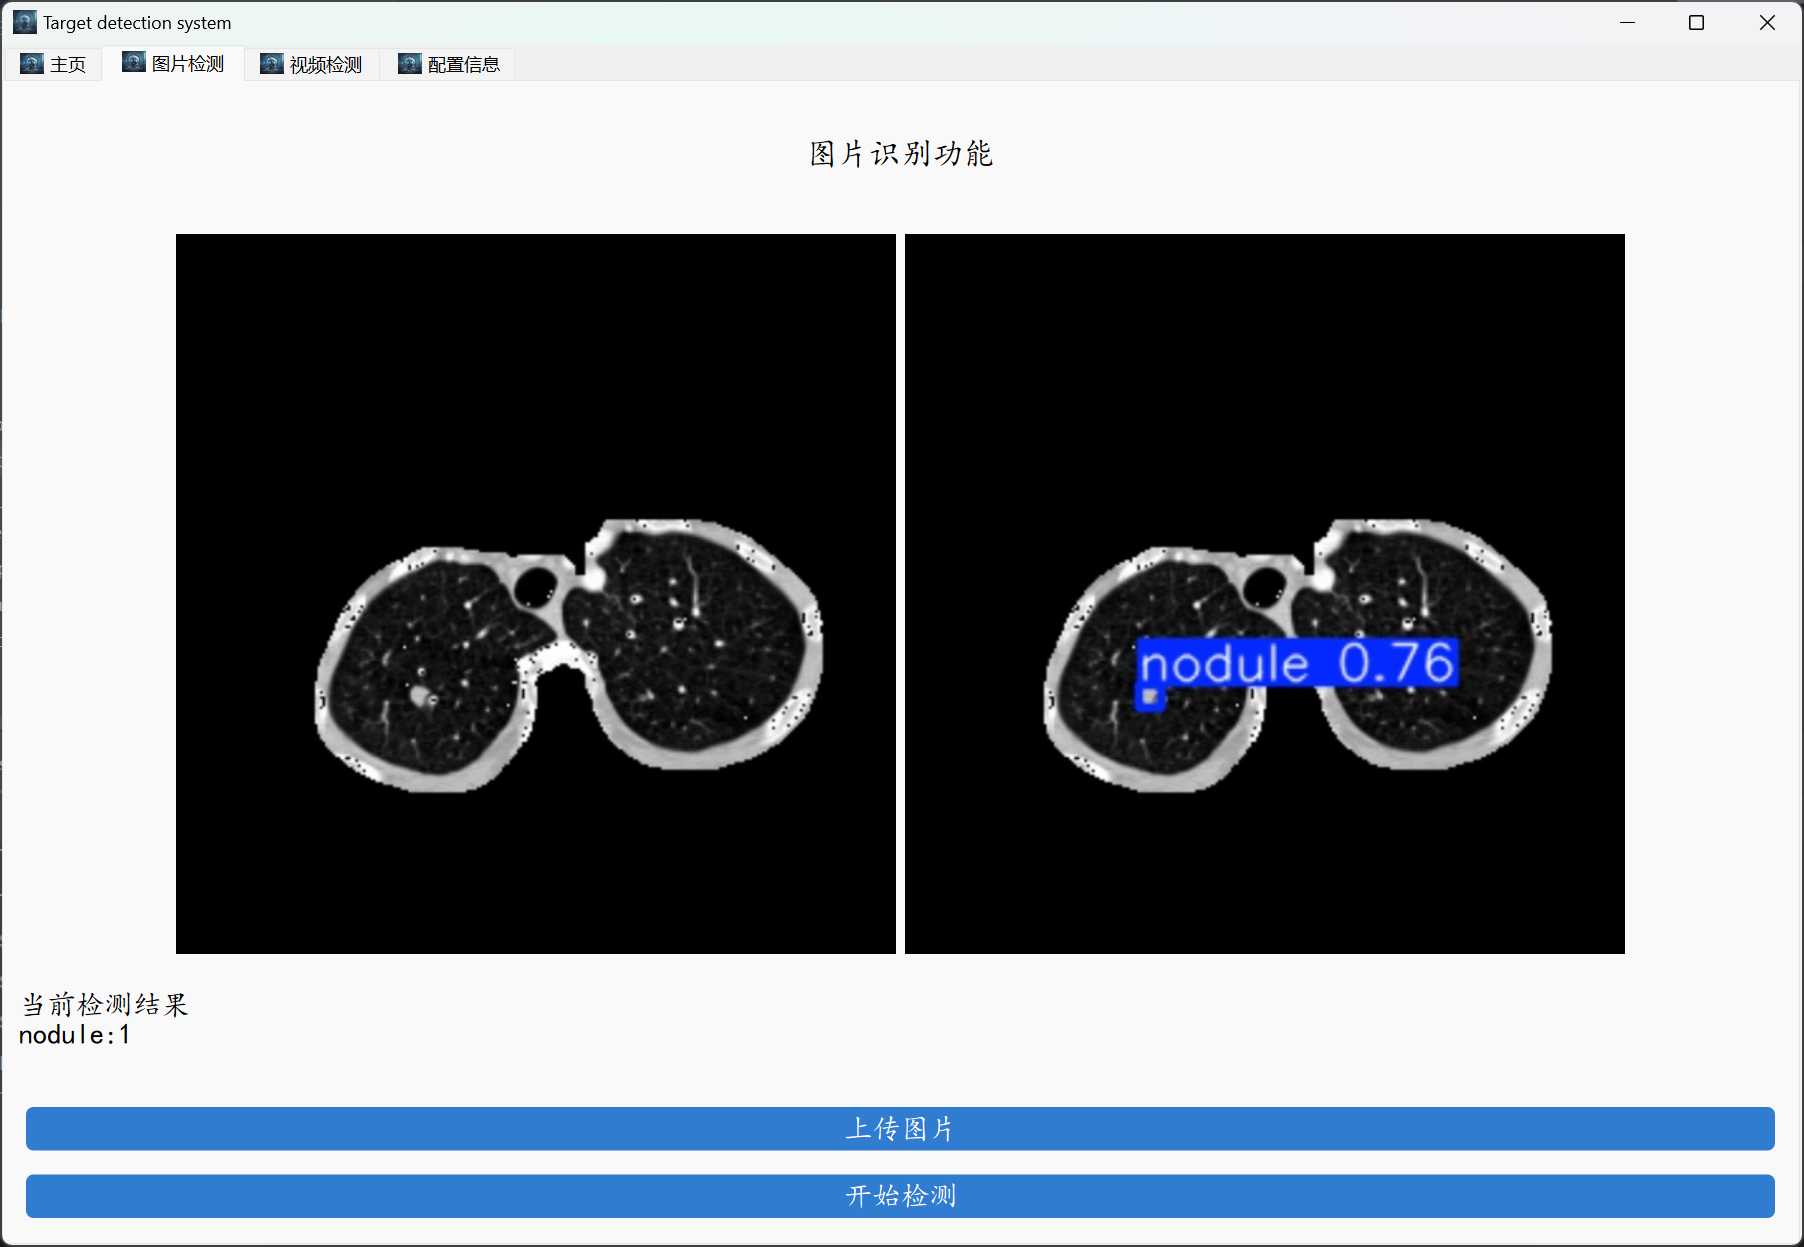

各位小伙伴,大家好,这里是肆十二,今天我给大家带了的是基于yolo11的肺结节检测系统,该系统使用luna16数据进行开发,一共包含有42个类的肺结节,我们分别基于yolov5、yolov8和yolo11进行了训练。本博客中我们将会按照教会大家对这个数据集进行训练、测试以及使用图形化的界面进行模型的加载来完成图像和视频的检测,效果图如下所示。

图形化界面封装

登录之后上传图像或者是上传视频进行检测即可。